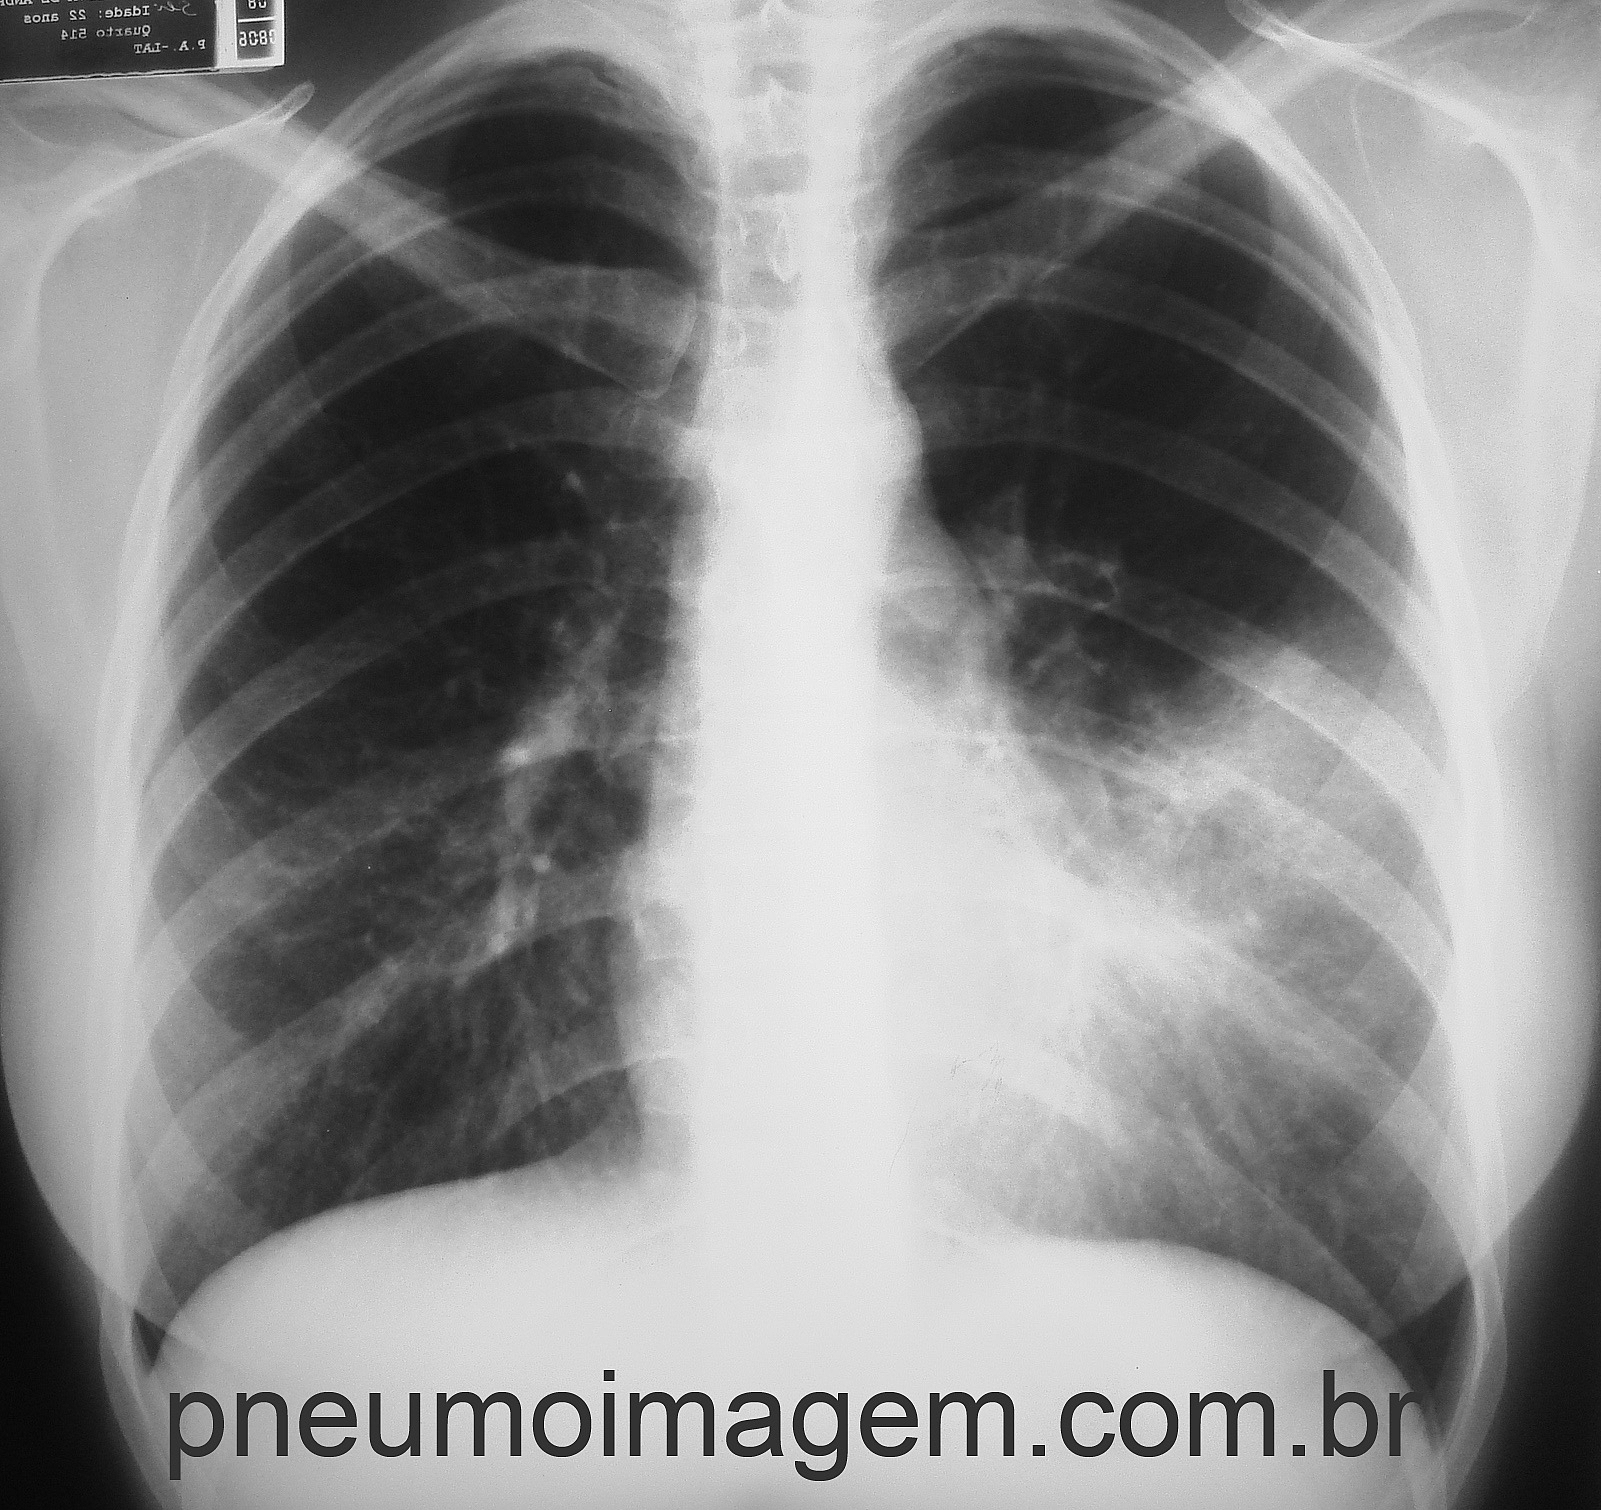

Veja imagens de PAC por patógenos atípicos no PneumoImagem, clique aqui.